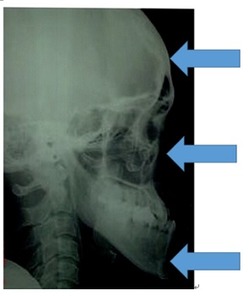

大人ではこの変化は起こりません。次に骨格で比べて診ましょう。

同じ人の1年後の骨格です。

小学校低学年の治療であれば、この変化は普通に起こる変化です。

骨格のことからも受け口は早期治療の効果が得られやすい症例です。

しかしながら20歳位まで受け口を放置すると下の図の様にその骨格は上から頭蓋骨は形を楕円に変形させます。中顔面は凹みます。下顎骨は先端部分が厚くなり、三角形になります。

このように、大人の咬合力で通常と逆に咬むために顔面頭蓋の骨の形を変化させて受け口に適応していきます。このため、大人になってから矯正治療は可能ですが変形した骨の形を元に戻す事は出来ません。

そのため、受け口の早期治療は価値があります。